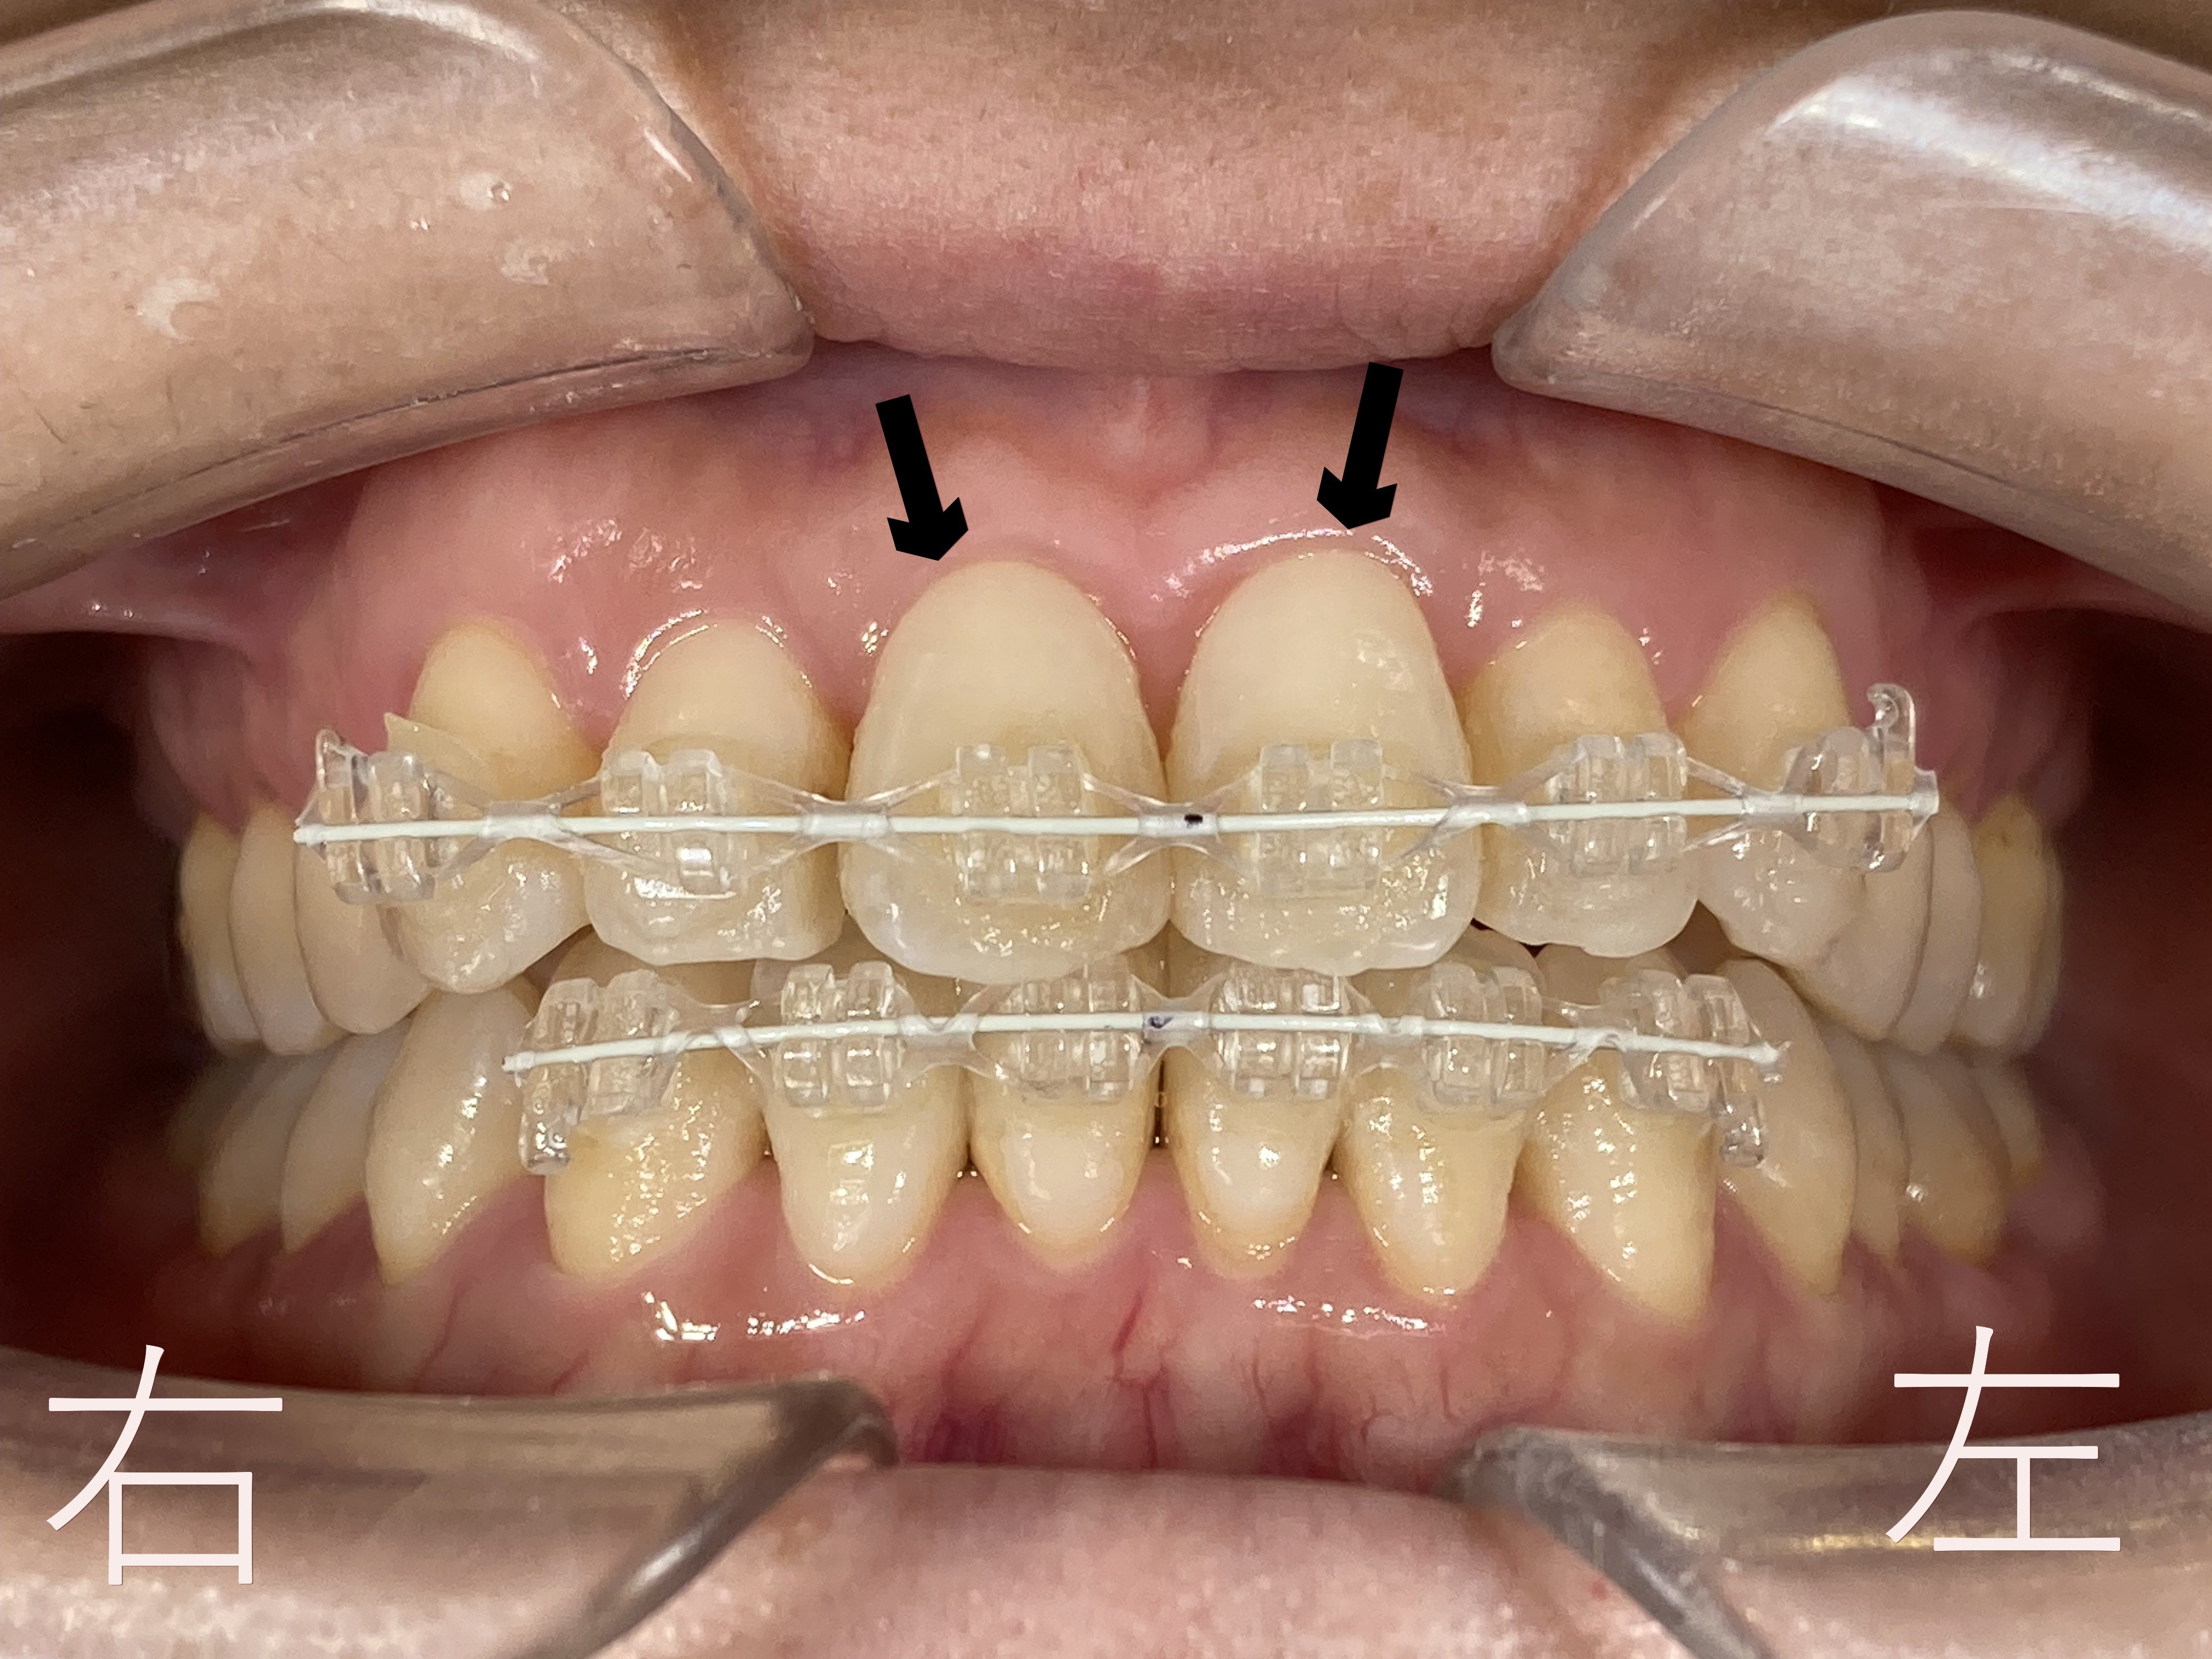

上記は8か月後の正面からみた写真です。上顎中切歯(黒色矢印)をご覧ください。

矯正前にあったゆがみ【叢生】が解消されています。

上記はボタン(マルチブラケット)を外した後の上顎左右中切歯(黒色矢印)の口腔内写真です。上顎左右中切歯のゆがみ【叢生】が解消していることが確認できます。